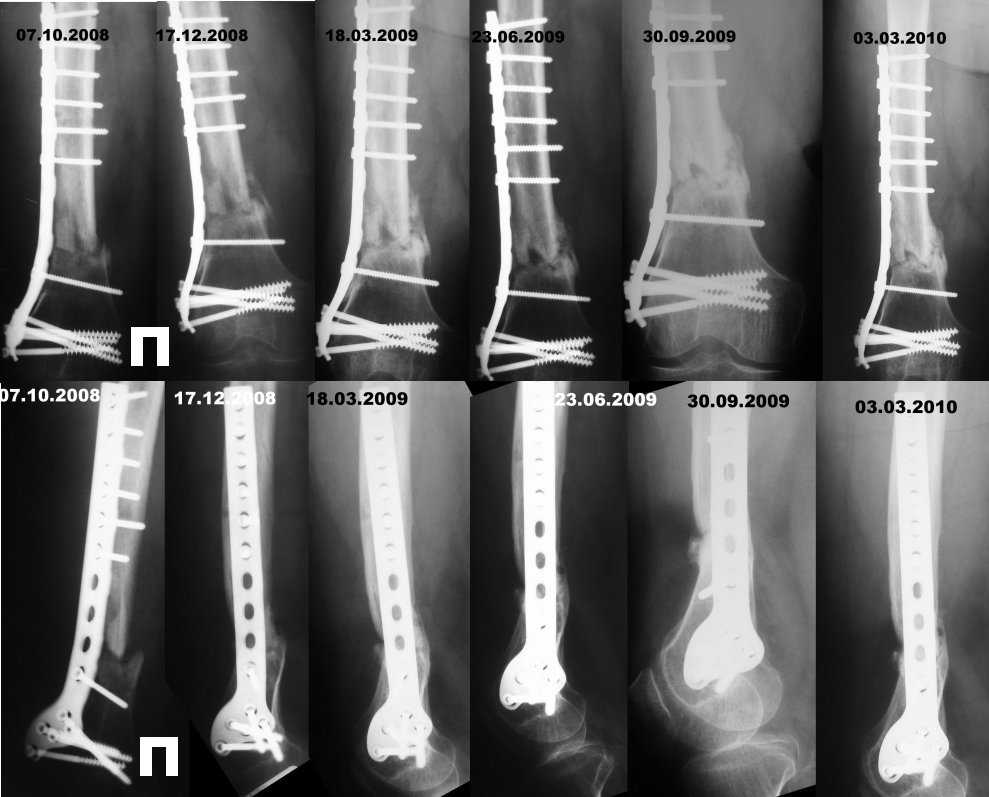

При поступлении 27.09.2009: На правом бедре ДКА, состоящий из 3-х колец, м/тк в области выхода спиц без признаков воспаления. Сосудисто-неврологических нарушений нет. Отмечается разгибательная контрактура правого коленного сустава, укорочение правой н/конечности на 5-бгсм.На представленных RG-граммах - оскольчатый перелом правого бедра на границе с/3 ин/3. синтез бедра ДКА, признаков консолидации не прослеживается.

30.09.2008 произведена операция; О/репозиция несросшегося перелома правого бедра, костная аутопластика. МОС мыщелковой пластиной.В послеоперационном периоде проведен курс а/6 терапии, гепаринотерапии, Рана зажила первичным натяжением» Сняты швы. Выписывается на амбулаторное лечение по месту жительства.

Описания двух последних Rg-граммамм:ДАННЫЕ ОБСЛЕДОВАНИЯ 30.09.2009 На rg-граммах бедра в прямой, боковой и косой проекциях: Состояние после МОС, костной пластики зоны оскольчатого перелома дистальной трети диафиза бедренной кости с фиксацией металлической пластиной и винтами. Формирование избыточной периостальной костной мозоли преимущественно по задне-медиальному контуру зоны перелома, хотя эностальная костная мозоль достоверно не визуализируется; линия перелома прослеживается. Прилежание металлической пластины к проксимальному отломку плотное, между дистальным отломком и пластиной прослеживается диастаз от 2-х до 4-х мм (при ретроспективном анализе Rg-грамм - данное положение фиксированной кости с 17.12.08). Учитывая практически полное отсутствие эностальной костной мозоли за длительный период времени и наличие диастаза между металлической пластиной и дистальным отломком бедренной кости - нельзя исключить элементы нестабильности на данном уровне - сочетать с клиникой.

ДАННЫЕ ОБСЛЕДОВАНИЯ 03.03.2010 В сравнении с Rg-граммами от 03.09.2009 - без значимой динамики. Несросшийся (в условии МОС металлической пластиной, костной аутопластики) оскольчатый перелом дистальной трети правой бедренной кости с признаками формирования ложного сустава (контуры отломков склерозированы, линия перелома прослеживается). Избыточная переостальная мозоль толко по задне-медиальному контуру отломков. Сохраняется диастаз от 2 до 4 мм между металлической пластиной и дистальным отломком. Признаки остеопенического синдрома на уровне коленного сустава.